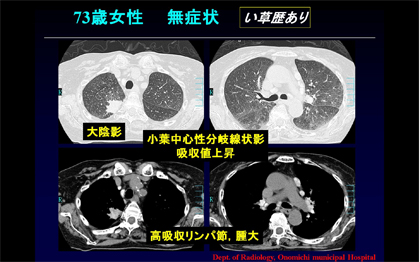

NMC Diagnosis。0b3b59392e9eaf6a38d2ac37cd75fc。間質性肺炎 | 印西そよかぜ内科・呼吸器内科。画像診断 Vol.41 No13. 特集『なぜによくわからない間質性肺炎。「肺炎の画像診断と最新の診療」藤田次郎定価: ¥ 12,540#藤田次郎 #本 #BOOK #健康 #医学